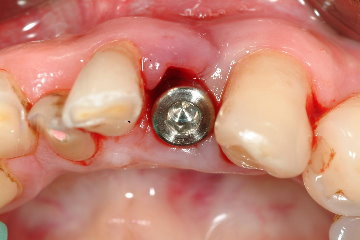

圖三為拔牙後的完整骨槽骨形狀,圖四為使用之Omni Tight人工植牙體,圖五為立即植牙後的情形,這時流血已完全停止,而齒槽骨與人工植第之縫隙再使用合成人工骨粉修復之,圖六為一週後牙肉之恢復情況

圖五 |